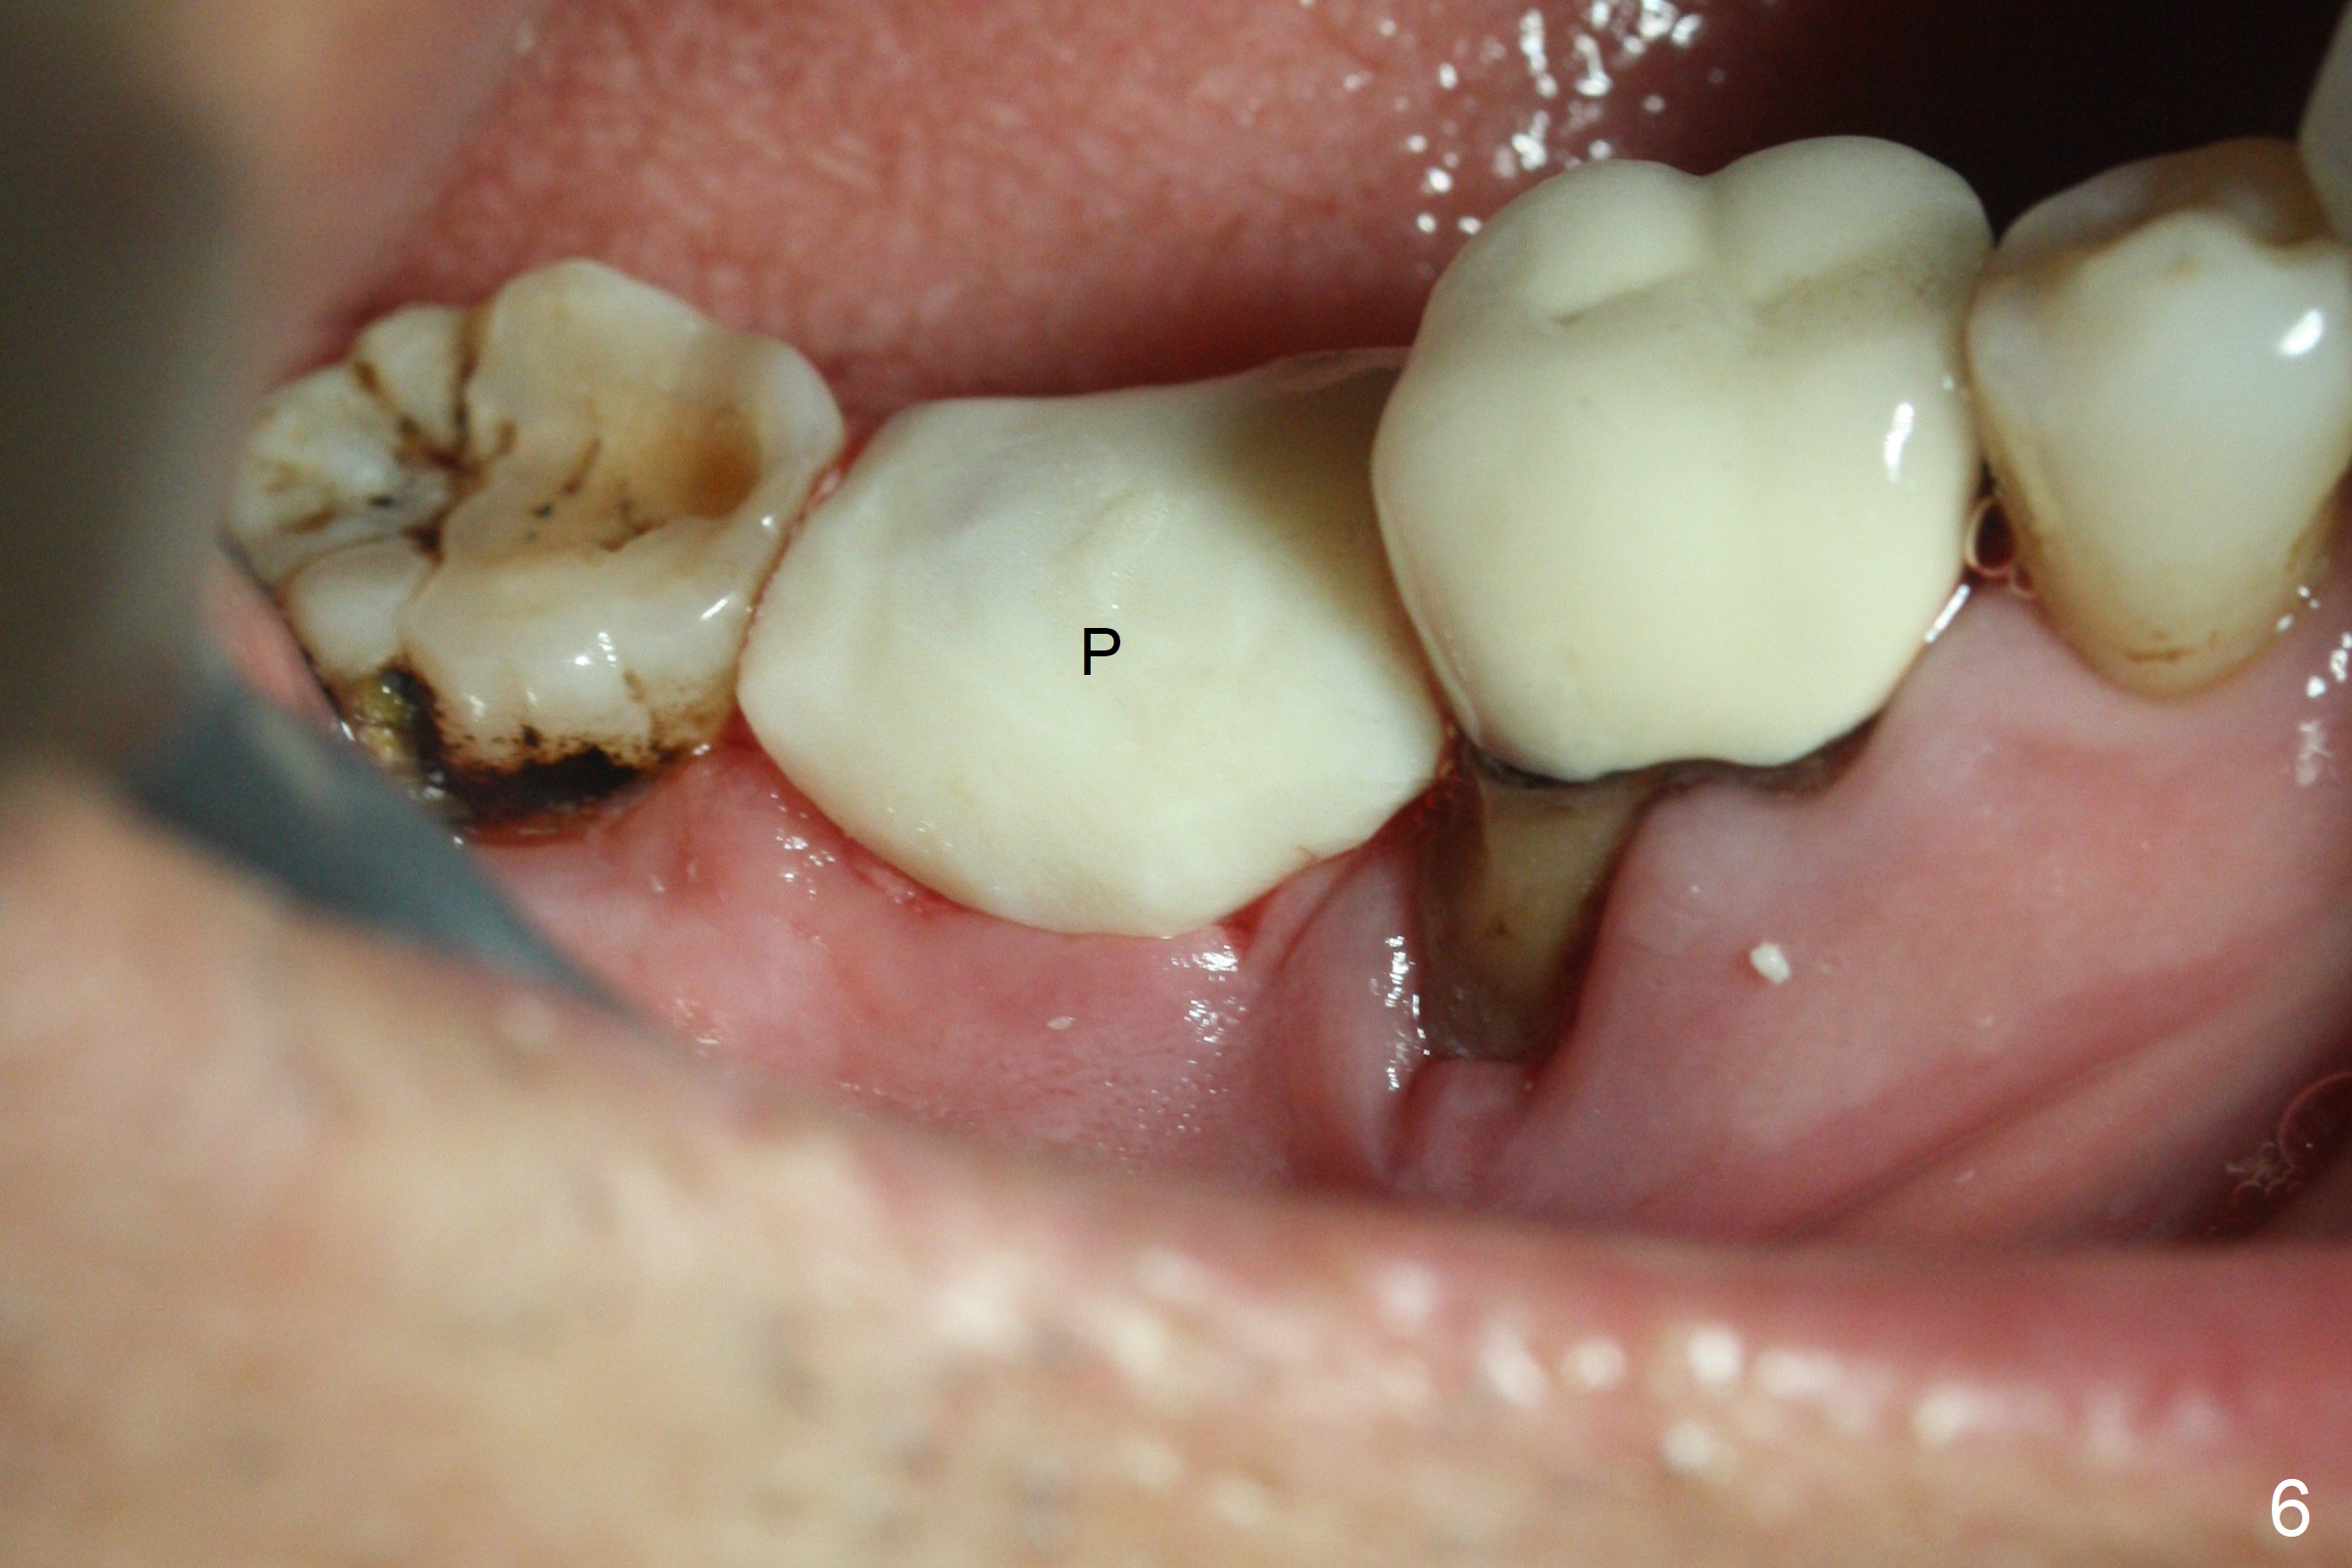

Although the tooth #30 has distobuccal root exposure (Fig.1 <), it is asymptomatic.  In contrast the tooth #31 with the distoocclusal caries (*) is symptomatic.  After use of 2 mm drill for 18 mm (lingual gingival margin), a calculated parallel pin is inserted (Fig.2 (D: 2 distal roots of the tooth #30)).  It appears that a 11.5 mm long implant is appropriate for the site; a 5 mm cuff is expected.  Following 4.8 mm drill, a 5.5x11.5 mm implant is placed initially (Fig.3) with an apical space (*) and clearance from the Inferior Alveolar Canal (red dashed line).  The implant is placed deeper with placement of a 6.5x4(5) mm abutment and bone graft (*, Fig.4,5).  After placement of collagen membrane over the graft, an immediate provisional is fabricated (Fig.6 P) with clearance from the opposing tooth (Fig.7 *).  There is no bone loss 3.5 months postop (Fig.8).  In fact the abutment has not been seated completely since its placement (Fig.4,5,8).  The crown/abutment dislodges 3 years 3 months post cementation (Fig.9).  The latter occurs for long incubation time because of opposing partial denture (Fig.10).  After trimming proximal surfaces (Fig.11: arrowheads), the abutment remains incompletely seated (Fig.11) due to possible crestal bone interference (Fig.11 *).  The smaller abutment by itself remains unseated (Fgi.12).  One size small one is completely seated (Fig.13).  Impression is taken.  Two weeks later the abutment margin is supragingival.  After screw torque at 20 Ncm, the crown is cemented with access hole.  Excess cement is removed.